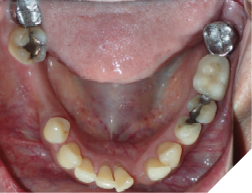

The majority of the orthodontic practices offer a period of “supervised retention” to their patients and communicates the customized retention recommendation with the patient’s general dentists. It is extremely important to work as a team to achieve long term clinical success in maintaining a functional bite and aesthetic smile. The general dentists continue to see their patients on a regular basis and have an opportunity to assess the orthodontic retainers and the bite after the supervised retention period is completed by the orthodontists. With great care, orthodontic retainers would serve for a long time (Fig. 1) without any major issues. However, in some cases, the failure to notice the clinical problems early on results in functional issues that would require a comprehensive orthodontic treatment to correct it (Fig. 2).

Fig. 2A

Fig. 2B

Fig. 2C